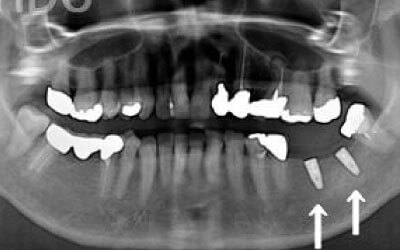

しばらくすると、抜けたままでも慣れてしまうことがありますが、その後に大きな問題が生じることがあります。

1 周囲の歯が早く抜ける

抜けた歯にかかるはずだった噛む力が、知らず知らずのうちに他の歯に負担をかけてしまいます。その結果、残っている歯が突然折れてしまい、抜歯が必要になることがよくあります。

2 歯が傾いてくる、落ちてくる

歯は互いに支え合い、バランスを保っています。そのため、歯が抜けると支えがなくなり、抜けた部分の両隣の歯が傾いたり、上の歯が下に移動してきたりすることがあります。